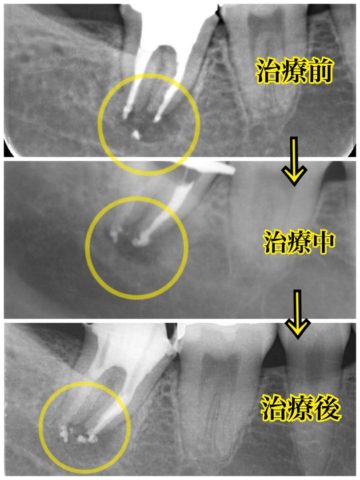

二次感染の取り残しについて